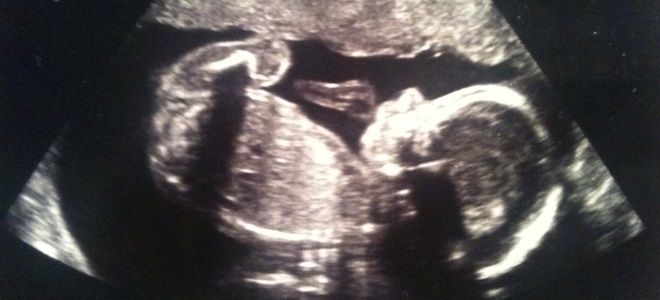

УЗИ НА 24 НЕДЕЛЕ БЕРЕМЕННОСТИ

Ультразвуковое обследование на двадцать четвертой неделе обычно проводится только по желанию самой женщины, чтобы определить развитие плода на двадцать четвертой неделе беременности, дать оценку его состоянию при выявлении определенных внутриутробных патологий.

Во время УЗИ врач оцениваетразвитие плода до 24 акушерской недели беременности – рост и вес плода, сердцебиение, развитие внутренних органов и головного мозга, двигательную активность, количество околоплодных вод, состояние плаценты и пуповины, а также наличие и отсутствие патологий развития.

На фото, которое можно получить после УЗИ, уже виден самый настоящий маленький человек. Выделяют несколько основных моментов.

Несмотря на то, что 24 неделя беременности – это очень важный период для развития ребенка, не исключены преждевременные роды. Но даже в этом случае специалисты смогут выходить малыша, если у него не будет серьезных патологий развития. Поэтому нужно вовремя делать УЗИ, которое позволяет не только сделать фото вашего ребёнка, но и определить возможные патологии на 24 неделе течения беременности.

УЗИ плода на 24 неделе беременности помогает не только определить состояние будущего малыша, но и осмотреть его внешне. На данном этапе внутриутробного развития будущая мама может сравнить его внешность, определить на кого похож. К этому времени лицевая часть головки уже полностью сформирована: губы, нос, разрез глаз будут иметь такой же вид, как и после рождения. Над веками можно рассмотреть брови. Ушки приподнимаются из-за роста головы и становятся в свое физиологическое положение.

Плод на 24 неделе беременности практически ничем не отличается от взрослого организма, только имеет меньшие размеры. Так длина его тела от темечка до крестца составляет 21 см, при этом рост будущего младенца вместе с ножками – 31 см. Вместе с ростом туловища происходит увеличение и окружности головки. На данном сроке она 5,9 см. Грудная клетка при этом не сколько больших параметров – 6-6,2 см. Практически такой же размер имеет и окружность живота – колеблется в пределах 6 см.

Плацента постепенно утолщается. К 24 неделе беременности развития плода ее толщина может достигать 2,6 см. С каждым днем мама четче ощущает шевеления малыша, его движения руками и ногами. Это обусловлено не только ростом плода, но и возрастающей его активностью. Совершенствуется координация движений, они становятся более произвольными: малыш может захватывать ручкой ножку.